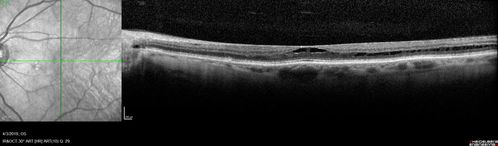

Stellate Non-heredtiary Idiopathic Foveomacular Retinoschisis (SNIFR)

77 year old man who is healthy and 6'6" tall with 20/40 vision and no complaints. OCT shows diffuse retinoschisis.